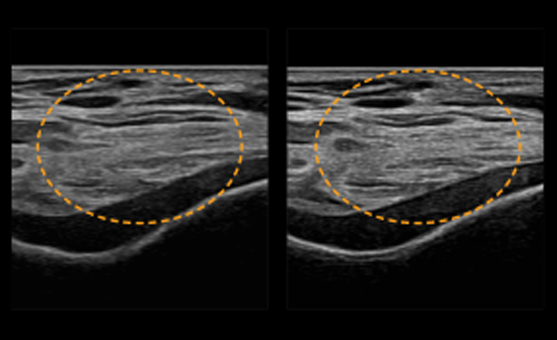

HQ-Vision oferă imagini mai clare prin atenuarea zonelor de imagine care sunt mai neclare decât natura lor reală

Filtrul de reducere a zgomotului îmbunătățește definiția marginilor și creează imagini 2D clare pentru performanțe optime de diagnosticare. În plus, ClearVision oferă optimizare specifică aplicației și rezoluție temporală avansată în modul de scanare în timp real.